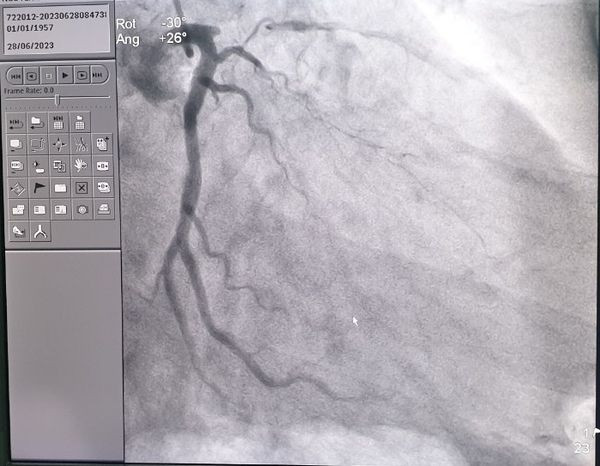

![]() |

| Phát hiện hẹp khít đoạn đầu động mạch liên thất trước |

Bệnh nhân đã được nhập viện, chụp động mạch vành phát hiện hẹp khít đoạn đầu động mạch liên thất trước, đã được can thiệp kịp thời, đặt 1 stent qua đoạn hẹp, sau đặt bệnh nhân ra viện ổn định.